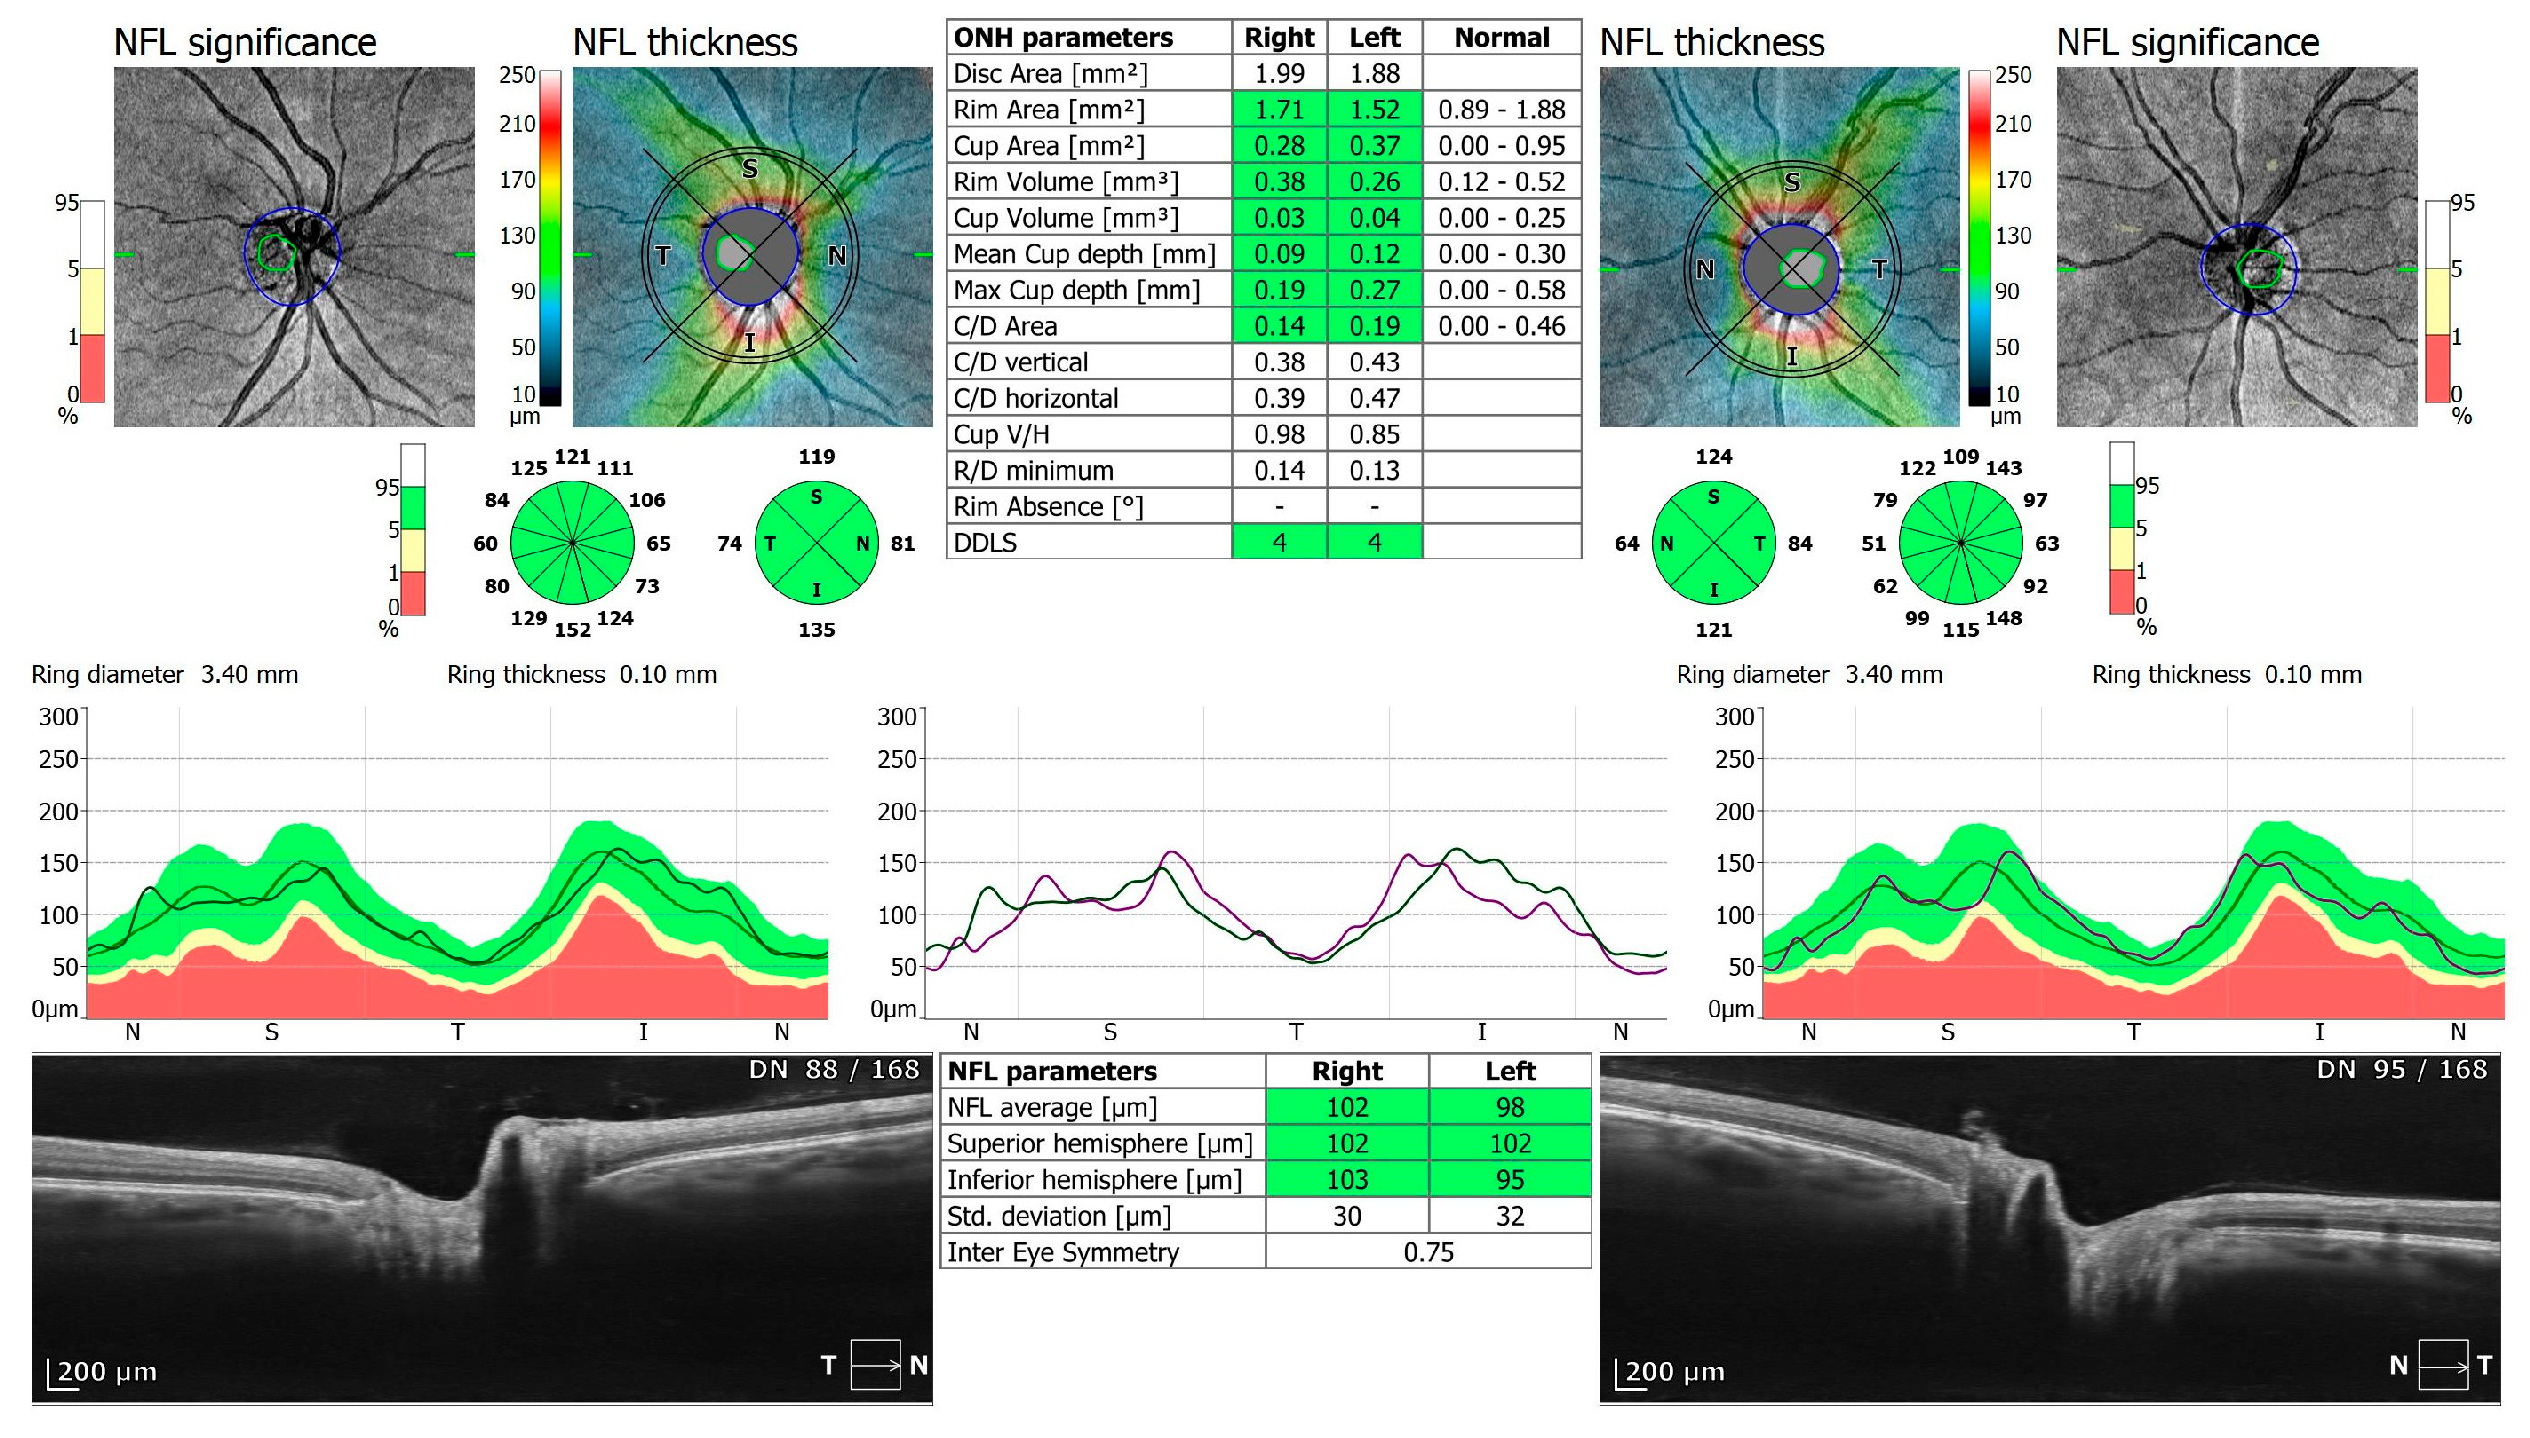

Figure 4.

OCT 3D disc scan 6 × 6 mm of COVID-19 negative patient. NFL, nerve fiber layer; ONH, optic nerve head.

Of the participants, 20 received oxygen therapy at flow rates ranging from 1–10 L, while 4 received high-flow intranasal oxygen therapy (HFNOT). Additionally, 5 patients were treated with Remdesivir therapy, 5 received COVID-19 convalescent plasma therapy, and 11 were treated with Tocilizumab. The demographics and clinical characteristics of the study participants are presented in Table 1. The mean time from a positive PCR test to study enrollment was 13.23 days, with a standard deviation of 8.18 days. The control group comprised 38 healthy individuals: 28 men and 10 women (control versus research group: p = 0.21), with an average age of 58 years, ranging from 33 to 69 years. All participants underwent two examinations, one upon admission and another upon cessation of therapy (6.70 ± 6.46 days). Spectral-domain optical coherence tomography (SD-OCT) was conducted using REVO FC 130 (Optopol Technology, Zawiercie, Poland). This device allows for high-resolution imaging and quantitative analysis of both the retina and cornea. The study specifically evaluated central retinal thickness, retinal nerve fiber layer (RNFL) thickness and optic disc parameters, alongside central corneal thickness and corneal epithelium thickness. The measurements were performed using built-in retinal and corneal layer segmentation tools provided by the OCT system, which automatically segmented the different layers of the retina and cornea to ensure precise and repeatable thickness measurements. OCT protocols included a 3D macula 7 × 7 mm scan, 3D disc 6 × 6 mm scan, and anterior radial 8 × 8 mm scan (Figure 1, Figure 2, Figure 3, Figure 4, Figure 5 and Figure 6). All patients had also undergone slit lamp examination, including indirect ophthalmoscopy.